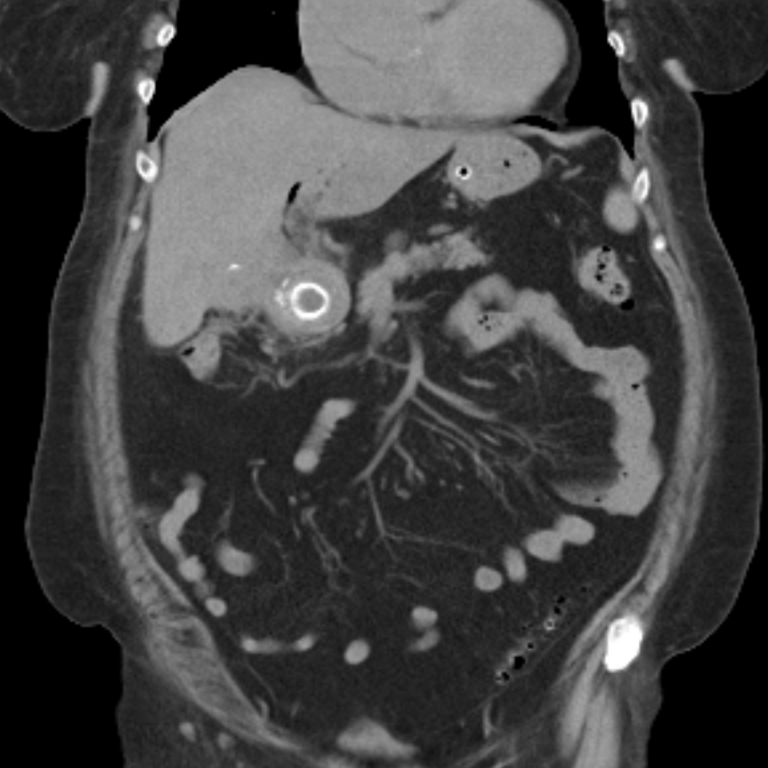

Синдром бувере

Синдром бувере 114 фото